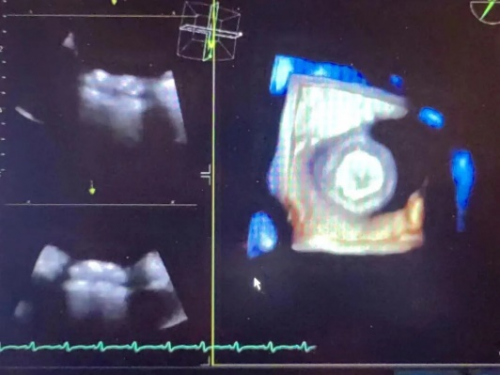

送入孔径6mm分流器释放于房间隔两侧,推拉试验确认分流器固定稳定、位置良好,透视下孔径符合预期目标,测量左房压25/10 (15) mmHg、右房压8/5 (6) mmHg、肺动脉压52/20 (31) mmHg,较植入前下降,左向右分流为少量,床旁超声可见分流器夹持于房间隔两侧。评估达到预期效果,释放分流器,患者血流动力学显著改善,手术成功。